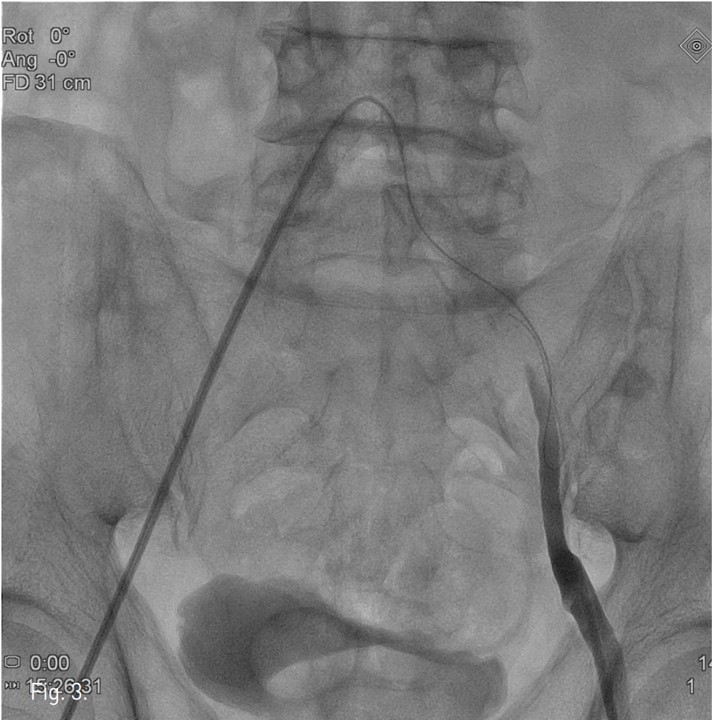

컴퓨터단층촬영 혈관조 영술과 고식적 혈관조영술에서 우측 총장골동맥에 석회화를 동반한 80%정도의 심한 협착이 있고, 좌측 총장골동맥에서 외장골동맥에 석회화를 동반한 완전 폐쇄의 소견이 있다 (Fig. 1A, IB). 우총대퇴동맥의 근위부에 10mm x 29mm Zenesis stent를 설치하였다 (Fig. 2). 0.035 inch guidewire로 좌측 총장골동맥의 기시부 폐쇄부위 통과를 시도하였으나 가성내강에서 진성내강으로 재진입이 되지 않았다 (Fig. 3). 좌측 외장골동맥 진성내강 내에 있는 ‘L-자’ 표시방향의 outback device가 보인다 (Fig. 4A), 좌측 외장골동맥 진성내강 내에 있는 'T-자’ 표시방향의 outback device가 보인다(Fig. 4B). Outback device를 이용하여 동맥내막을 천자후 0.014 inch guidewire를 가성내강 내로 진입시켰지만 좌측 총장골동맥-외장골동맥경 계부위에서 더 이상 진행되지 않았다 (Fig. 4C). 0.014 inch guidewire를 따라서 Davis catheter를 가성내강 내로 진입시키고 (Fig. 5A), 10mm snare를 삽입하여 Simmon catheter내부에 있던 microwire를 전진시켜 snare로 잡아 좌측 sheath로 뽑아내어 (Fig. 5B), 5Fr. Davis catheter를 대동맥 내부로 진입시켰다(Fig. 5C). 양측 총장골동맥 및 좌측 외장골동맥 스텐트 설치후 대동맥장골동맥조영술상에서 양측 장골동맥의 완전한 재개통을 보인다 (Fig. 6).

Fig. 1. A

Fig. 1. Enhanced coronal CT angiography MIP image and conventional aortoiliac angiography show about 80% occlusion at right common iliac artery and complete occlusion at left common iliac artery and external iliac artery.